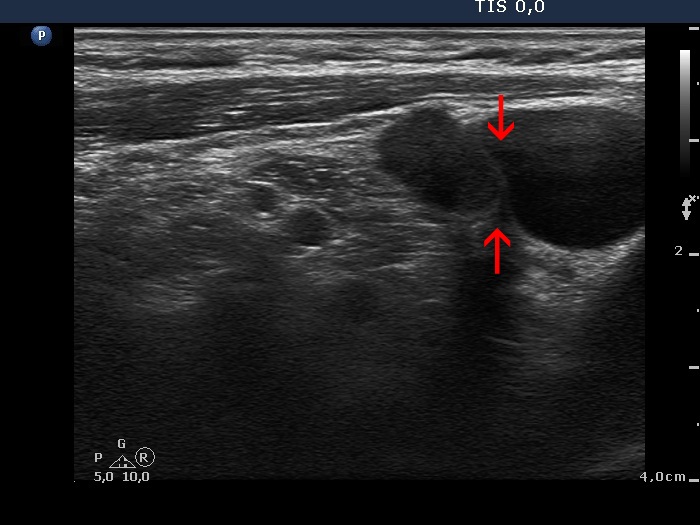

Ultrasonography: the right thyroid was echonormal while the left lobe contained moderately hypoechogenic areas with a 50% echogenicity index. There was a hypoechogenic mass lower and lateral to the right thyroid. The lesion did not present a regular hilum.

Palpation: a firm node lateral and lower to the right thyroid.